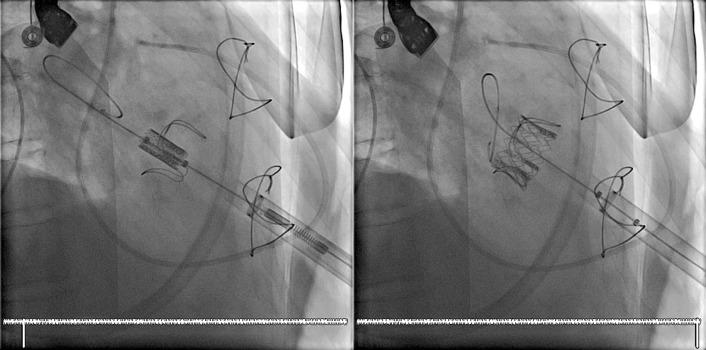

Transcatheter/percutaneously inserted heart valves are increasingly implanted. Most commonly, they are inserted into the pulmonic position or right heart conduits in the previously repaired congenital heart disease population ( Figs. 13-1 and 13-2 ) and into the aortic position ( Table 13-1 ; Graphics 13-1 and 13-2 ; Figs. 13-3 to 13-10 ), but they can also be placed into atrioventricular valve positions and into bioprostheses or conduits in any position.

Percutaneous valves are generally supported by radiographically obvious stents, the design of which allows for initial contraction of the prosthesis onto a catheter and release/self-expansion from the catheter.

Percutaneous/transcatheter heart valves are constructed of either bovine jugular venous valves that are suspended on wire mesh cages (Bonhoeffer design/Melody Transcatheter Pulmonary Valve–TPV, Medtronic), or consist of a valve created from bovine pericardial tissue that is suspended on wire mesh cages (Edwards Sapien and Medtronic CoreValve). Percutaneous aortic valve implantation is currently one of the most rapidly proliferating percutaneous interventions in the world ( Figs. 13-11 to 13-13 ).